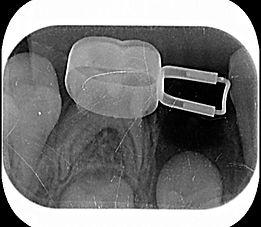

X光片可見本院高品質的根管治療水準。